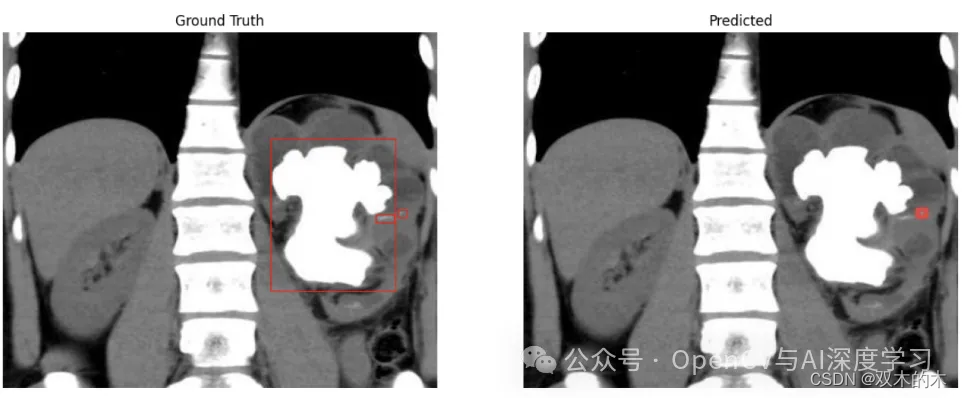

示例一:大肾结石(漏检)

观察:在此示例中,模型无法从输入图像中检测到较大的肾结石。结石的形状比通常的结石要大,而且结石的形状看起来也不规则。